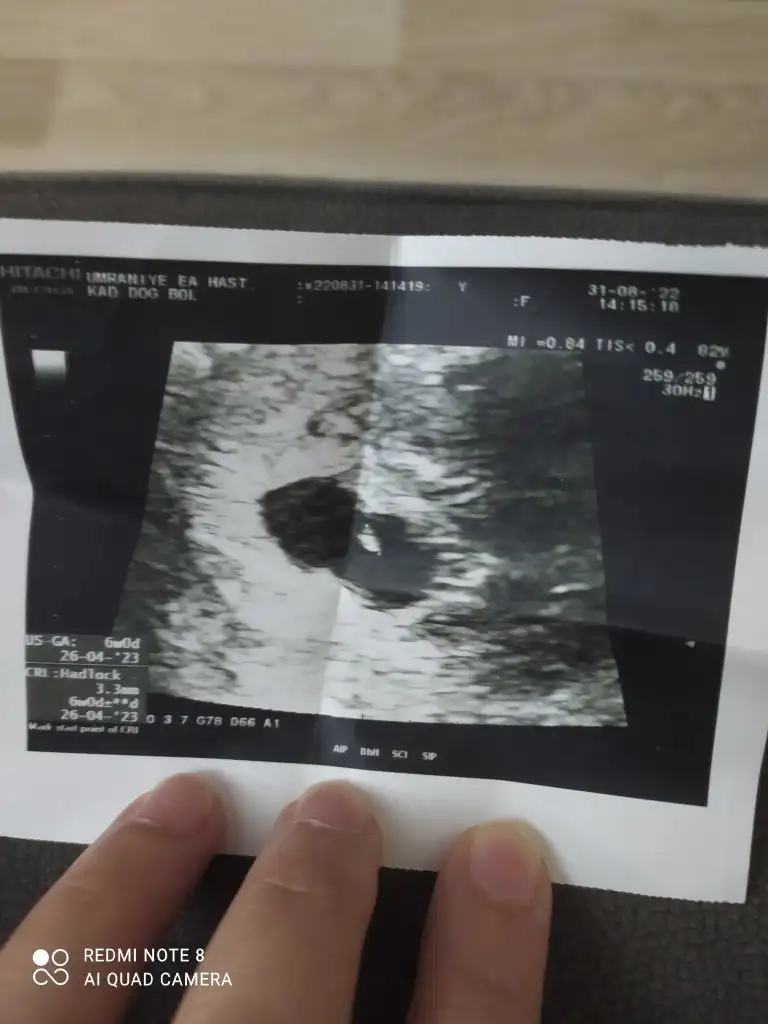

Ama bu ultrasondan sonra dedim bu kız.

Bu hafta fetal yaptıracağım ve en geç 10 güne öğreniciiizz

Benimde solda ama kesede fasulye gibi umut ediyorum kiz olmasını bakalım cinsiyetler belirlenince hangi teoriler tutmuş olacakSolda ama kese yuvarlak değil sankiahh bir umut belki kız olur

İkimizin aynı cinsiyet olmalı o zaman hadi bakalım nasıl olacak acabaBenimde solda ama kesede fasulye gibi umut ediyorum kiz olmasını bakalım cinsiyetler belirlenince hangi teoriler tutmuş olacak